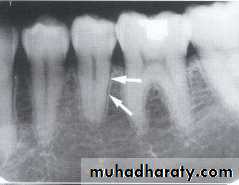

MANDIBULAR CANAL:

The mandibular canal is a tube like passage way through the bone that travels the length of the mandible, its extends from the mandibular foramen to the mental foramen and houses the inferior alveolar nerve and blood vessels. On radiograph the mandibular canal appears as a radiolucent band outlined by two thin radiopaque lines that represent the cortical wall of the canal.